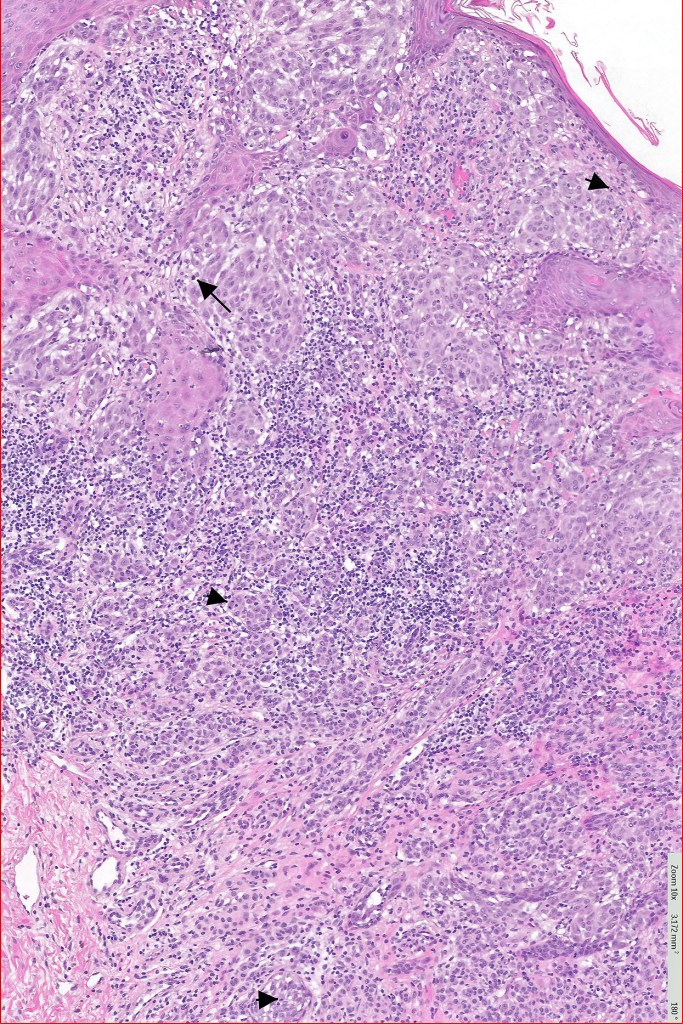

Histological features

•>5-10 mm

•Involve deep dermis or subcutis

•Asymmetrical, poorly circumscribed

•May show effacement/consumption of epidermis or ulceration

•Peripheral Pagetoid spread

•Large nodules which often show impaired maturation

•Loss of gradient with HMB45 and Ki67

•>20% Ki67 expression

•TERT promoter & PTEN mutations

•DNA copy-number variations